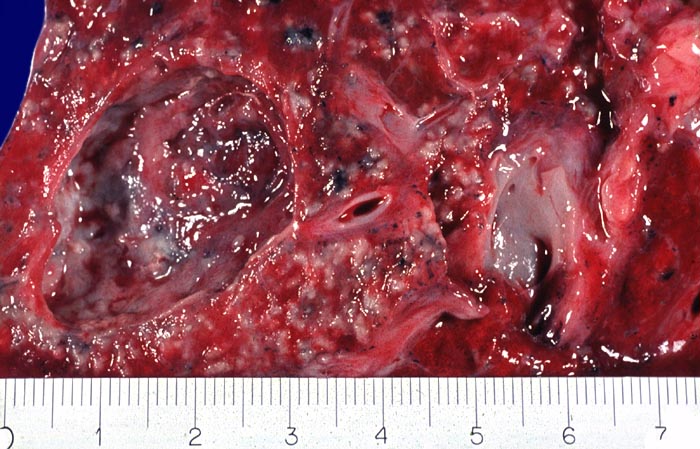

Das morphologische Bild ist äusserst variabel. Je nach Abwehrlage, Art und Geschwindigkeit der Ausbreitung entstehen unterschiedlich grosse, teils geschichtete Herde mit unterschiedlichem Grad an Epitheloidzellreaktion, zentraler Nekrose bzw. Vernarbung. Rein produktive Granulome ohne Nekrosen sind Zeichen guter Abwehrlage. Der Begriff Verkäsung bezieht sich auf den makroskopischen Aspekt von Nekrosen, der an Frischkäse erinnert. Exsudative nekrotisierende Granulome entstehen bevorzugt bei schlechter Abwehrlage. In späteren Stadien der Lungentuberkulose unterscheidet man produktive Phthisen mit azinös nodösen Gruppen von bronchogen entstandenen gering verkäsenden Streuherden (Präparat), zirrhotische Phthisen mit gering verkäsenden stark vernarbenden Herden und exsudative Phthisen bei schlechter Abwehrlage. Bei letzterer steht die Verkäsung im Vordergrund. Die bakterienreichen Herde entstehen teils hämatogen, teils bronchogen. Verkäsende Herde sind Ausgangspunkt für die Kavernenbildung. Kavernen stellen die wichtigste Quelle für die bronchogene Streuung dar.

• Tuberkulöse Herde ausgehend von vollständig oder partiell entzündlich zerstörten Bronchiolen in unmittelbarer Nachbarschaft von Arterien.

Makroskopie